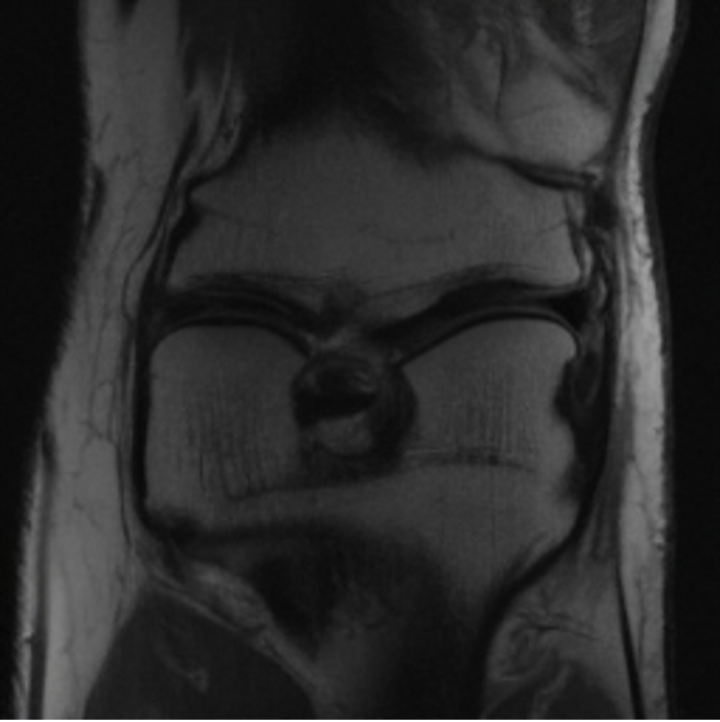

5.3 Out-of-Domain Generalisation

One way to test the generalization capability of the trained X-Diffusion is to test it on a completely different domain from an MRI dataset not seen during training. We report the single-slice results on NYU fastMRI [37, 82], a knee MRI dataset, using the X-Diffusion trained on the BRATS brain MRIs. The results are shown in Figure 9 and Table 2. It shows how successfully X-Diffusion is able to generate knee MRIs from a single image, despite not seeing knees at all in training. To qualitatively assess how realistic our generated 3D volumes were (produced from a single slice), we gave 20 generated examples alongside their real MRI counterparts to an expert orthopaedic surgeon. He was then asked to identify the real example from a given pair. The surgeon identified with certainty only 10 real knee MRIs out of 17, while could not decide on the remaining 3 of the 20 MRI pairs. This further validates the generated out-of-domain MRIs.